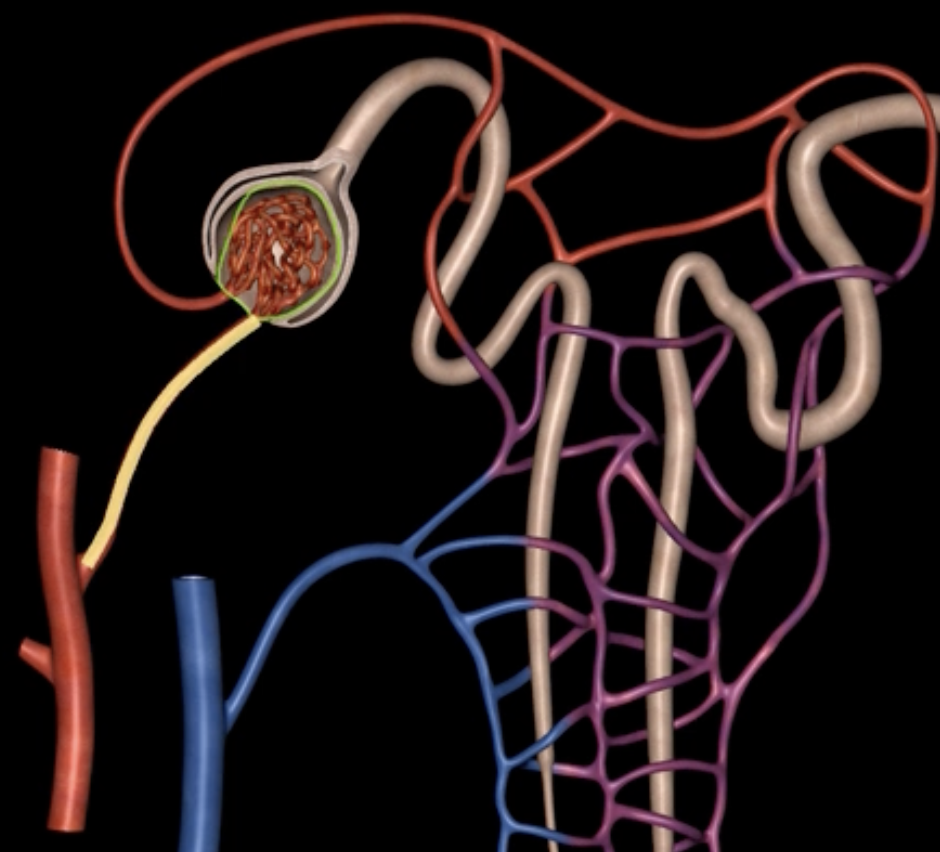

afferent arteriole

yellow

glomerulus

green

efferent arteriole

purple

orange: peritubular capillaries

green: vasa recta

efferent arteriole give rise to orange and green

green: renal corpuscle

purple: renal tubule

green:

purple:

blue: glomerulus

orange: Bowman’s capsule

blue:

orange:

blue: visceral layer

red: parietal layer

red: